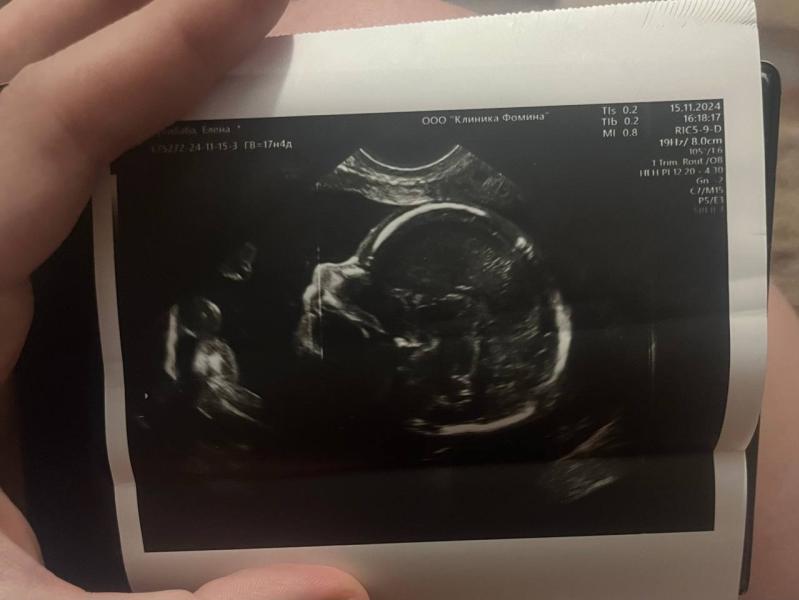

Впереди был второй скрининг, мы решили пройти его платно. И у нас появились прекрасные кадры нашей малышки с 3Д узи.

Она была красавицей, уже тогда увидели, что очень похожа на папу.

Делали в Клинике Фомина. УЗИ шло почти час, мне показали каждый орган, каждую клеточку. Все объяснили и рассказали.